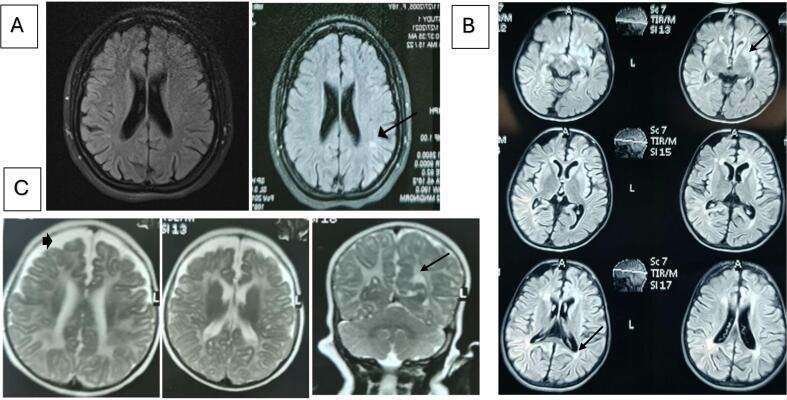

A cohort study was conducted at the metabolic clinic of Children Welfare Teaching Hospital in Baghdad from the 1st of December 2021 to the 1st of December 2022. The study included fifteen patients who met the following criteria: (1) elevated serum homocysteine levels (>15 μmol/L); (2) low or normal blood methionine levels (12-40 μmol/L). fourteen MTHFR patients underwent statistical analysis, and one CblC patient was assessed separately. MTHFR patients comprised nine females and five males. The mean age at presentation was 7.1 years ±4.5, ranging from 1 to 16 years. Consanguineous marriages were reported in 13 patients. A family history of a similar disorder was documented in 73 % of cases. Among the families, four had two affected siblings. The two main reported clinical manifestations were gait disturbance (10/14, 71.4 %) and cognitive impairment/intellectual disability (6/14, 42.8 %). Brain MRI was conducted for all studied patients, with leukodystrophy being the most common finding (8/14, 57.1 %). Molecular testing revealed variants in in 14 patients, and in one patient.

于2021年12月1日至2022年12月1日在巴格达儿童福利教学医院代谢门诊进行了一项队列研究。该研究纳入了15名符合以下标准的患者:(1)血清同型半胱氨酸水平升高(>15μmol/L);(2)血液蛋氨酸水平低或正常(12 - 40μmol/L)。对14名甲基四氢叶酸还原酶(MTHFR)患者进行了统计分析,对1名钴胺素C(CblC)患者进行了单独评估。MTHFR患者包括9名女性和5名男性。就诊时的平均年龄为7.1岁±4.5岁,范围为1至16岁。13名患者报告有近亲结婚情况。73%的病例有类似疾病的家族史。在这些家族中,有4个家族有两名患病的兄弟姐妹。报告的两个主要临床表现是步态障碍(10/14,71.4%)和认知障碍/智力残疾(6/14,42.8%)。对所有研究患者进行了脑部磁共振成像(MRI)检查,最常见的发现是脑白质营养不良(8/14,57.1%)。分子检测在14名患者中发现了变异,在1名患者中也发现了变异。